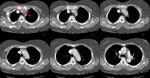

A chest CT was dome due to the severity of the patients symptoms. The

scan demonstrated an aortic dissection involving both the ascending and

descending aorta. The images of the chest revealed that the dissection

extended into the great vessels arising from the aortic arch (red arrows).